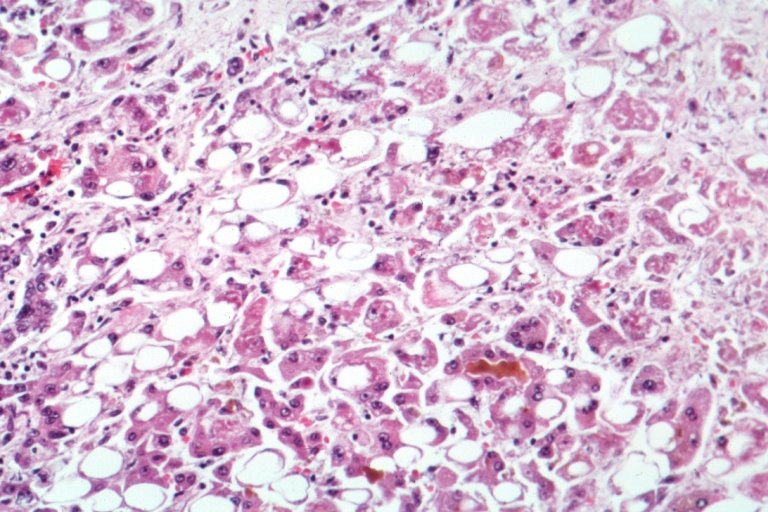

알코올성 간염의 조직 검사 소견, 다수의 지방세포(흰색) 출처 : 위키피디아

알코올성 간염은 간세포가 파괴되고 간에 염증이 있는 상태입니다. 식욕감소, 구역, 구토, 복통, 체중 감소 등의 증상이 있으며 심한 경우에는 황달, 복수 등의 증상이 발생할 수 있습니다.

간 기능 검사(AST, ALT 등)에서 간 기능 저하 소견(AST, ALT 상승)이 보일 수 있습니다. 알코올성 간염의 초기에는 금주하면 호전이 가능하지만, 중등증 이상이 되면 알코올성 간경변증으로 진행할 수 있습니다.